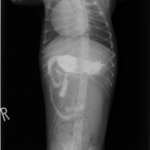

9歳 チワワ 4.8kg

主訴:2日前の夜に桃の種を飲み込んだとのこと。元気・食欲に問題はなく、嘔吐などの消化器症状もみられなかった。誤飲した当日に他院にて催吐処置を試みたが、吐き戻さなかったとのこと。

単純レントゲン検査:明らかな異常所見なし

消化管バリウム造影レントゲン検査:胃内にて異物の存在を疑う異常所見を認めた。

造影直後

内視鏡検査:内視鏡下にて、バスケット鉗子を用いて胃内異物を摘出。

異物内容:桃の種 (約4cm大 写真上)、とうもろこしの芯 (約2.5cm大 写真下)

本症例は、床に落としてしまった桃の種を誤飲していました。動物の体格に対して異物が非常に大きく、開腹手術となる可能性があった症例でした。また、桃の種と一緒に出てきたとうもろこしの芯は、日々のおやつとして与えていたものということでした。とうもろこしの芯は非常に硬く、小さく切って与えても消化されず、長期間胃内に残ってしまうことや腸閉塞の原因となる為、注意が必要です。